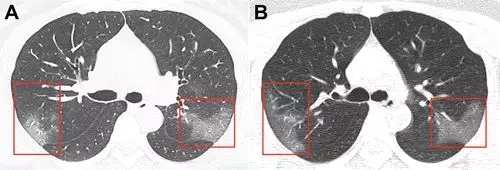

病例1,33岁女性,在武汉工作,

今年1月份回到兰州后

第二天开始发热,咳嗽,

5天后,她去医院检查,

她咽喉部分泌物中发现新冠病毒核酸,

肺部CT扫描(见下图A)

两侧肺上叶肺段呈斑片状毛玻璃样显影。

医生给她用了很多药物,

甚至用上了干扰素,

3天后,再次CT检查发现,

两肺的毛玻璃显影更大了(图片B),

显示治疗效果不好,病情加重。

图片来自《Radiology》杂志